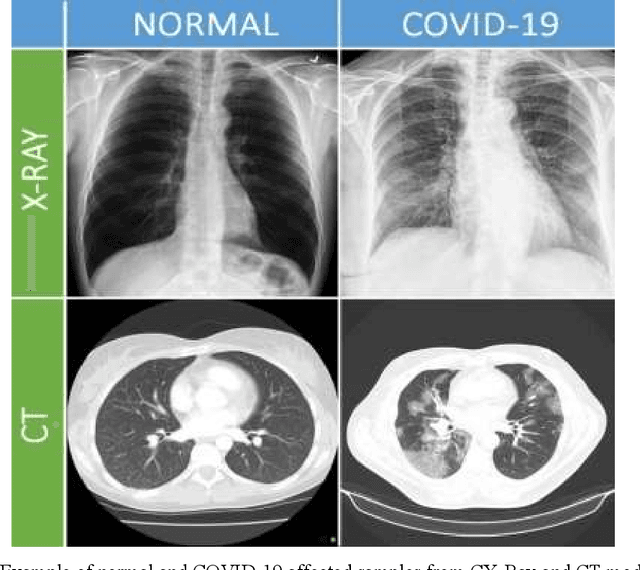

Abstract:The Coronavirus (COVID-19) outbreak in December 2019 has become an ongoing threat to humans worldwide, creating a health crisis that infected millions of lives, as well as devastating the global economy. Deep learning (DL) techniques have proved helpful in analysis and delineation of infectious regions in radiological images in a timely manner. This paper makes an in-depth survey of DL techniques and draws a taxonomy based on diagnostic strategies and learning approaches. DL techniques are systematically categorized into classification, segmentation, and multi-stage approaches for COVID-19 diagnosis at image and region level analysis. Each category includes pre-trained and custom-made Convolutional Neural Network architectures for detecting COVID-19 infection in radiographic imaging modalities; X-Ray, and Computer Tomography (CT). Furthermore, a discussion is made on challenges in developing diagnostic techniques in pandemic, cross-platform interoperability, and examining imaging modality, in addition to reviewing methodologies and performance measures used in these techniques. This survey provides an insight into promising areas of research in DL for analyzing radiographic images and thus, may further accelerate the research in designing of customized DL based diagnostic tools for effectively dealing with new variants of COVID-19 and emerging challenges.